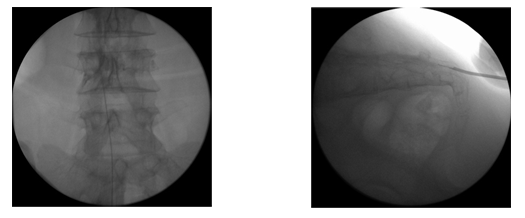

°æÇÇÀû ôÃßü ¼ºÇü¼ú°ú ºñ½ÁÇϳª 3ÁÖ°£ÀÇ Àû±ØÀû º¸Á¸Àû Ä¡·á¿¡µµ Áõ»óÀÇ È£ÀüÀÌ ¾øÀ» °æ¿ì ÂîºÎ·¯Áø °ñÀý ºÎÀ§¿¡ ³¡¿¡ dz¼±ÀÌ ´Þ¸° ±ä Ư¼ö ±â±¸¸¦ »ðÀÔÇÏ¿© dz¼±À» ºÎÇ®·Á ³ôÀ̸¦ º¹¿øÇÑ ÈÄ¿¡ '°ñ½Ã¸àÆ®'¸¦ ÁÖÀÔÇÏ´Â ½Ã¼ú·Î ÀåÁ¡Àº ³ôÀ̸¦ ¾à°£ ȸº¹½Ãų ¼ö ÀÖ°í Á» ´õ µÈ »óÅÂÀÇ ½Ã¸àÆ®¸¦ ÁÖÀÔÇÒ ¼ö ÀÖ¾î ½Ã¸àÆ® À¯ÃâÀÇ À§Ç輺À» ÃÖ¼ÒÈÇÒ ¼ö ÀÖ½À´Ï´Ù.